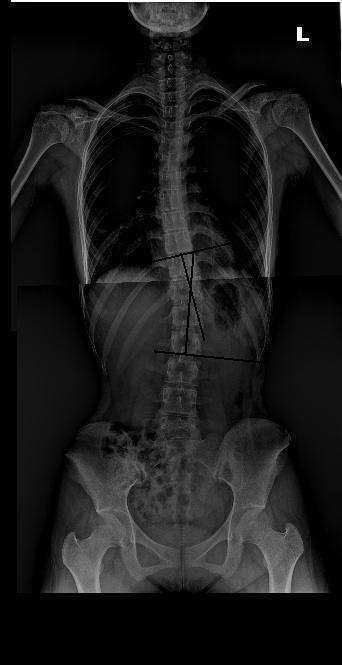

척추측만증을 수술 하지 않고도 치료 할 수 있나요?

측만증은 단순히 어느 하나의 치료로 효과적인 결과를 보이기 어려우나 치료효과가 좋은 경우는 추나요법으로도 만족할 만한 결과를 보이기도 합니다. 그래서 조기진단과 조기치료가 중요하다고 할 수 있습니다.

추나요법을 통해 틀어진 척추를 바로 잡고 바태운동으로 체형 교정운동을 병행하여 바로 잡힌 척추에 새로운 근력을 생기게 하고 침이나 기타 요법으로 경락의 흐름을 좋아지게 하면 측만증은 호전되고 개선됩니다.